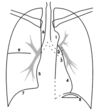

The pattern of how you will scan each lung on a CXR.

A